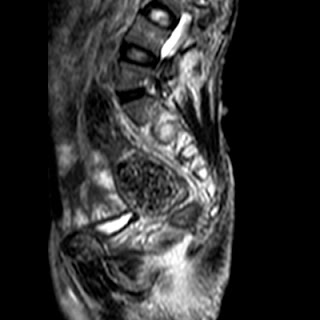

Radiological images (MRI):